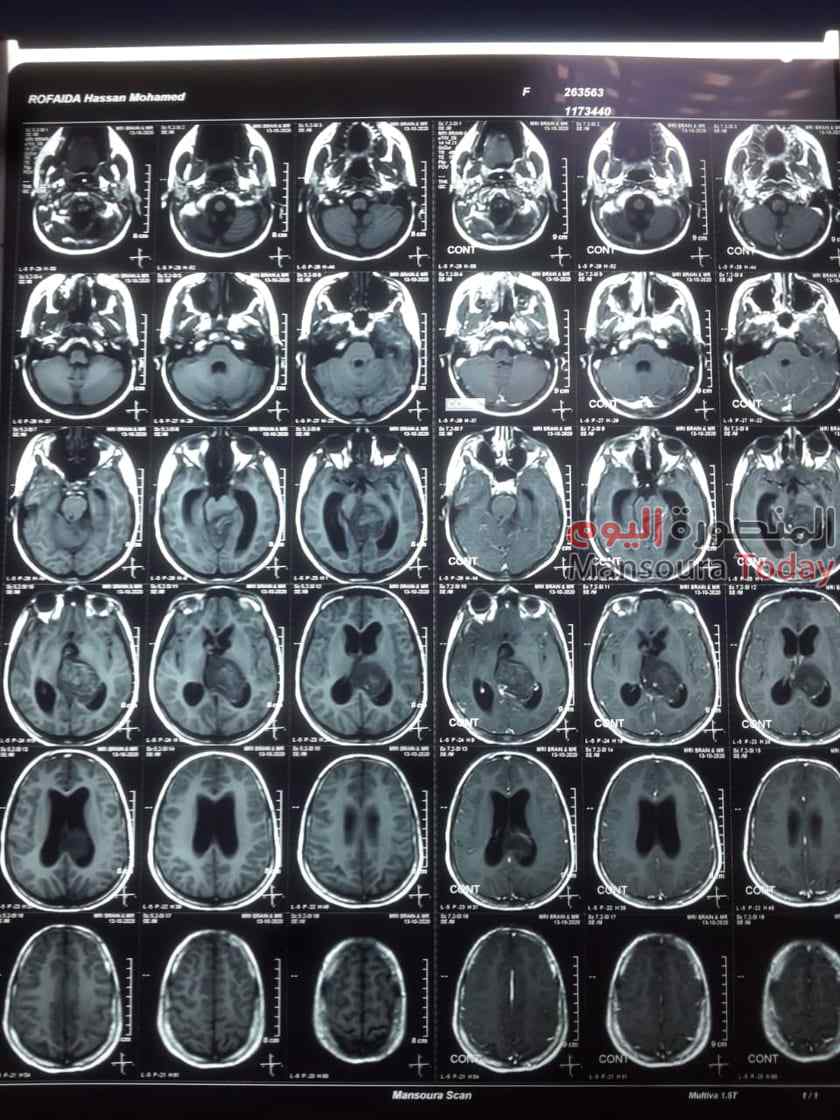

أعلن اليوم الدكتور سعد مكى وكيل وزارة الصحة بالدقهلية عن انجاز جديد لصحة الدقهلية، حيث نجح فريق طبي فى سابقة هي الأولى من نوعها فى مستشفيات وزارة الصحة بإنقاذ حياة طفلة تبلغ من العمر 11 عاما كانت تعانى من نزيف ببطينات المخ ادى الى تدهور شديد فى درجة الوعى لارتفاع ضغط السائل النخاعى على جذع المخ ، و تم التدخل الجراحي العاجل من الفريق الطبى وعمل الجراحة بطريقة بسيطة باستخدام جهاز ( CVP) بتحويل مسار السائل تحت فروة الرأس ventricluosubgaleal shunting وقد استغرقت العمليه حوالي خمس ساعات ،. وهي تعد من العمليات المتقدمة ذات المهارة الخاصة. الجدير بالذكر أن المعتاد فى السابق في مثل هذه الحالات ان يتم تركيب صمام مخى بريتونى دائم مما قد يؤدى الى مضاعفات فى تلك الحالات او تركيب صمام لخارج المخ فى جهاز تجميع خارجى قد يؤدى إلى التهابات بالسحايا المخية .